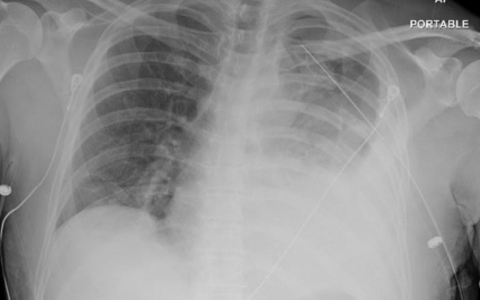

A 28-year-old woman presents to her physician with concerns that she is unable to produce breast milk, despite having given birth approximately one month ago. On further questioning she indicates she has been exceptionally thirsty lately, and describes feelings of fatigue and cold intolerance. Physical examination reveals no abnormalities except a scarcity of axillary hair. Laboratory tests reveal a serum sodium level of 150 mEq/L and urinalysis reveals a urine osmolality of 220 mOsmol/kg. Which of the following most likely increased the patient’s risk of developing this condition?

一名28岁的女性到她的医生处就诊,担心她无法产生母乳,尽管她大约一个月前已经分娩。在进一步的询问中,她表示她最近特别口渴,并描述了疲劳和不耐冷的感觉。体格检查除腋毛稀少外无其他异常。实验室检查显示血清钠水平为150 mEq/L,尿液分析显示尿液渗透压为220 mOsmol/kg。下列哪一项最有可能增加患者患这种疾病的风险?

该患者表现为席汉综合征或产后垂体坏死,由分娩时出血引起。危险因素包括多胎妊娠(双胎或三胎)和胎盘异常。围产期出血使已经增大的垂体发生缺血,导致部分垂体前叶和(或)垂体后叶坏死。席汉综合征最常见的临床特征是由于垂体前叶受损和泌乳素生成减少而导致的不能分泌乳酸。其他症状包括甲状腺功能减退症(如患者对寒冷的不耐受),以及由抗利尿激素产生减少引起的中枢性尿崩症(DI)。DI表现为在血清钠水平升高的情况下出现多尿和稀尿。FSH和LH水平降低常导致闭经和阴毛和腋毛生长不足。治疗包括对所有缺乏的激素进行终身激素替代疗法,同时补充雌激素和孕激素。

正确答案:A